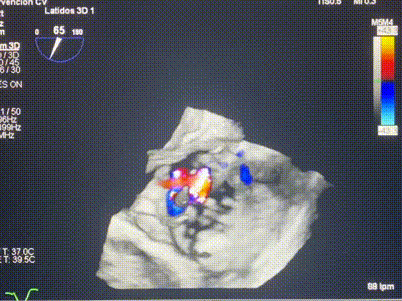

術(shù)中輸送器在超聲引導(dǎo)下調(diào)整位置

手術(shù)在全麻狀態(tài)下進(jìn)行。術(shù)者采用經(jīng)右側(cè)頸靜脈入路的方式將輸送器送入患者心臟內(nèi),在TEE及DSA引導(dǎo)下調(diào)整輸送器頭端角度,使得輸送器與三尖瓣瓣環(huán)平面垂直。在輸送器進(jìn)入右心室后釋放室間隔錨定裝置,而后釋放瓣葉夾持件(2個耳片結(jié)構(gòu))成垂直狀態(tài)。在TEE及DSA確定夾持件固定至三尖瓣葉根部且位于右室側(cè)后釋放人工瓣心房側(cè)盤片。隨后調(diào)整瓣膜同軸性以及室間隔錨定件位置(貼合室間隔),前推藏針管并固定,進(jìn)而釋放室間隔錨定裝置,并再次確認(rèn)瓣膜位置、穩(wěn)定性及同軸性,合攏輸送鞘后撤出輸送器,完成LuX-Valve Plus人工三尖瓣瓣膜的植入,僅殘余微量瓣周漏。且經(jīng)手術(shù)中心電生理團(tuán)隊評估,病人的起搏器和ICD功能沒有受到影響。